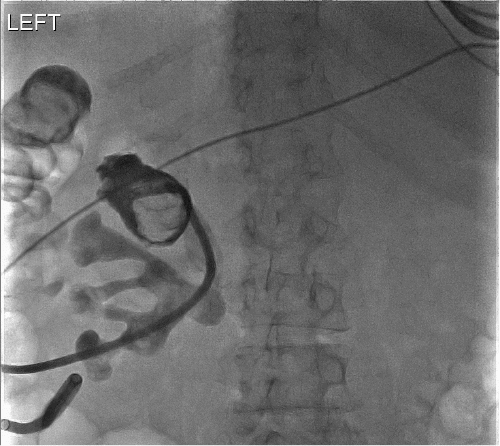

Figure 2. Intraoperative CT Images Showing Fistula, Renal Calculus, and Fungal Ball. Published with Permission

A) Immediate filling of fistula from left middle pole calyx into descending colon

B) filling defect in left upper pole calyx consistent with fungal ball or abscess ball